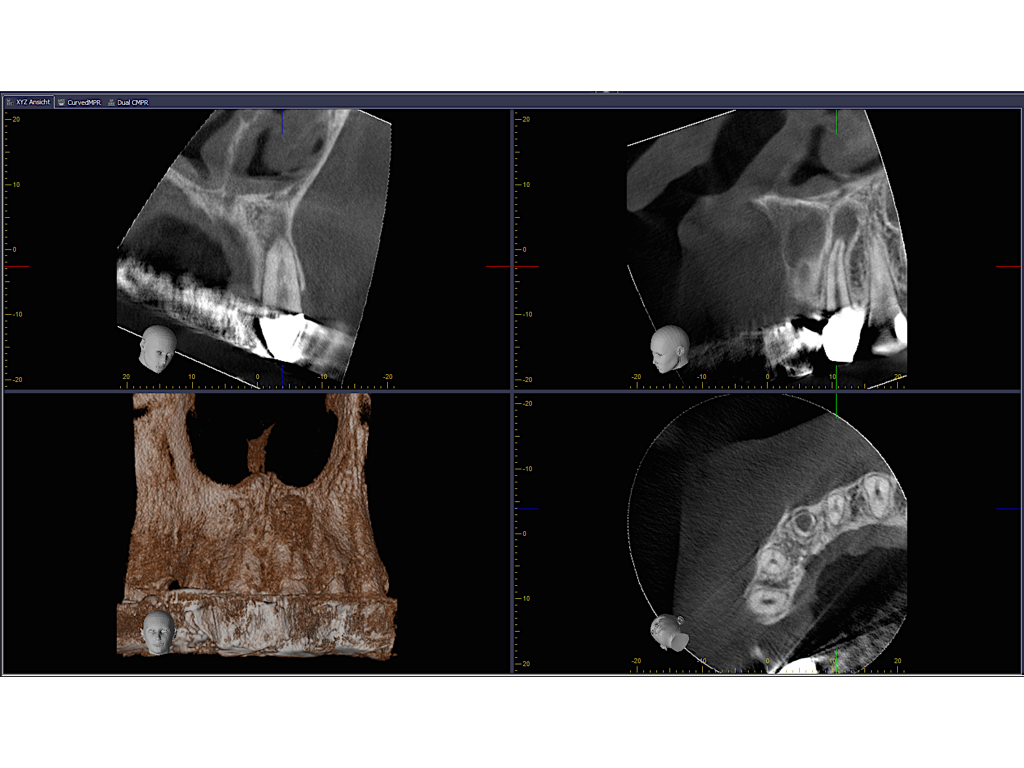

WS9_7_15.003

Saving hopeless teeth (37)